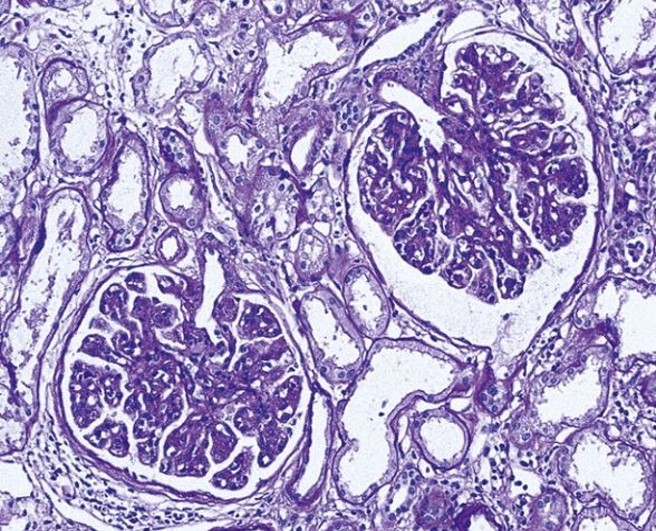

What is this and why?

MPGN due to increased cellularity and pronounced “lobularity”